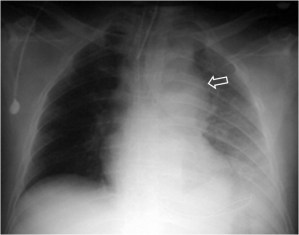

SIGNO DE LA ALTERACIÓN DEL CONTORNO AÓRTICO

La irregularidad, abombamiento o borramiento del arco aórtico en la radiografía de tórax en bipedestación o en decúbito supino, en un paciente con traumatismo torácico, obliga a descartar rotura aórtica como causa de dicha alteración. La flecha muestra el contorno aórtico anómalo. Además, hay un aumento de densidad en el hemitórax izquierdo correspondiente a derrame pleural –hemotórax en este caso-, que refuerza la sospecha de rotura aórtica.